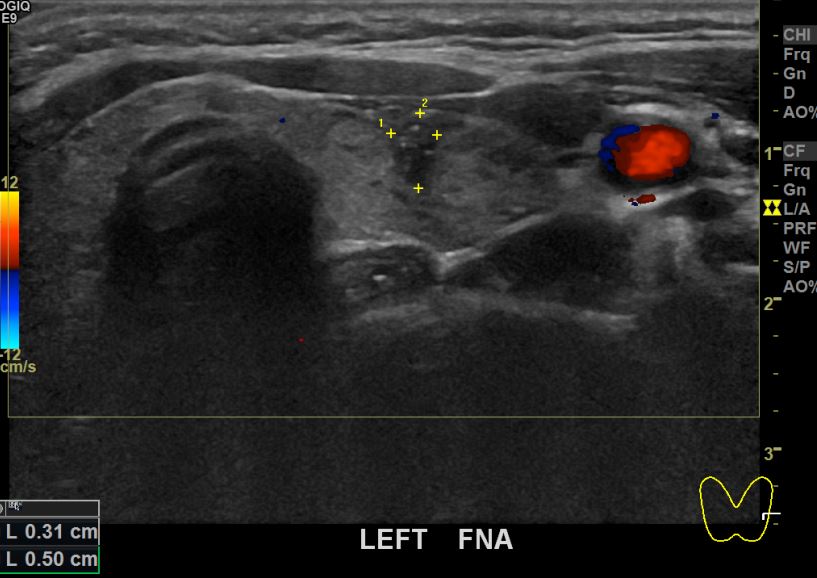

상기환자 건강검진상 이상소견으로 내원하신 30대초반 여성분으로 좌엽 의심스러운혹

세포검사진행후 갑상선암으로 진단되었습니다